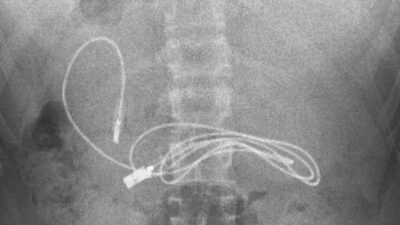

15 yaşındaki çocuğun midesinden çıkanlar şaşkına çevirdi! 1 metrelik şarj kablosu da var